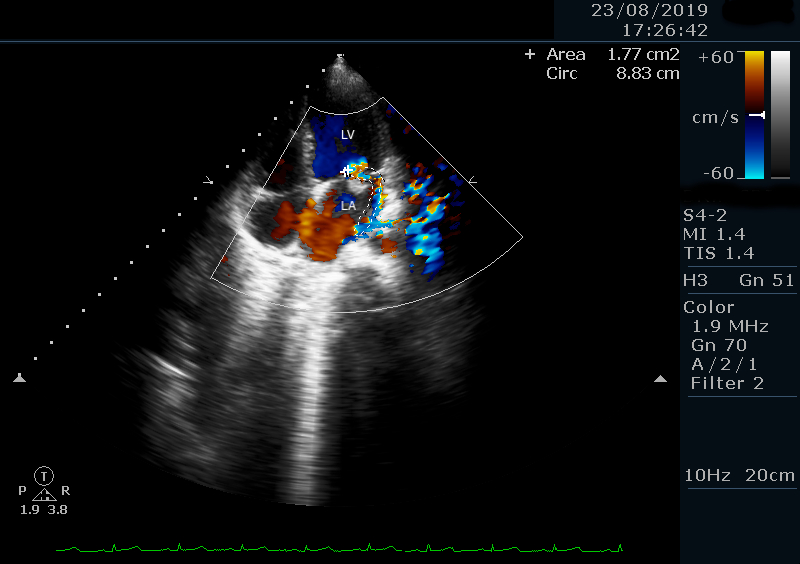

A previously healthy 6-year-old girl from a rural, socioeconomically disadvantaged background presented with a 2-week history of persistent high-grade fever, fatigue, and poor oral intake. She had no prior cardiac or chronic illnesses. Initial management for presumed enteric fever was unsuccessful. On admission, she was febrile (38.5°C), tachycardic (110 bpm), normotensive (90/70 mmHg), and had a grade III/VI pansystolic murmur. The rest of the exam was unremarkable. Labs showed leukocytosis (WBC 17,500/μL) with neutrophilia and elevated inflammatory markers. Chest X-ray and abdominal ultrasound were normal. Transthoracic echocardiography (TTE) revealed a mobile 11 mm vegetation on the anterior mitral leaflet with severe mitral regurgitation (Figure 1). Blood cultures grew methicillin-resistant Staphylococcus aureus (MRSA). IV vancomycin and gentamicin were initiated. No anticoagulation was given. Cranial CT and neurologic assessment were normal. After 14 days, repeat TTE showed a reduction in vegetation size to 8 mm. She remained afebrile and clinically improved. Antibiotics were continued for 6 weeks. A follow-up echo 4 weeks post-discharge showed complete resolution of the vegetation with persistent moderate mitral regurgitation (Figure 2). No embolic or neurologic events occurred. At 3-year follow-up, TTE confirmed no vegetation recurrence and stable MR (Figure 3) .